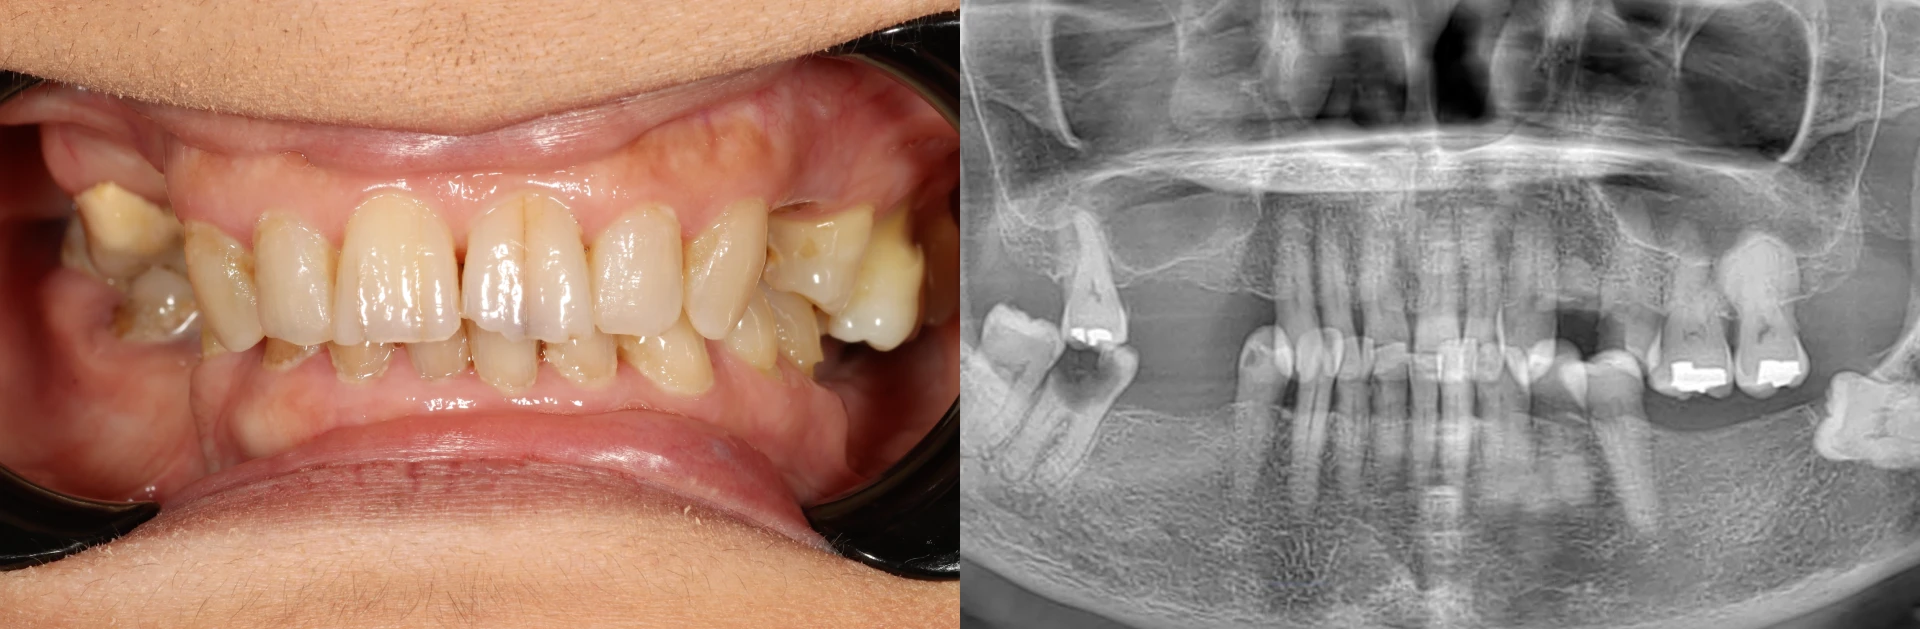

A patient's smile before all on 4 dental implants, including a panoramic x-ray showing missing teeth and decay.

• Missing Back Teeth: Like many patients, she had lost her back molars first. This forced her to chew with her front teeth, which are not designed for the heavy forces of grinding food, leading to a cascade of other problems.

• Damage to Front Teeth: The excessive pressure on her front teeth led to chips, visible cracks, and significant wear that compromised their strength and appearance.

• Widespread Cavities: Large cavities were present in several of her remaining teeth. These teeth were too decayed to be saved with fillings or crowns, making them unsalvageable.

• Hyper-Eruption: Some of her upper teeth, with no opposing lower teeth to bite against, had drifted down into the empty space. This dental issue makes the teeth non-functional and eliminates the room needed to place new teeth on the bottom arch.

• Aesthetic Concerns: She was unhappy with the gray and yellow staining, visible plaque and calculus buildup, and the overall look of her smile, which made her hesitant to smile fully.